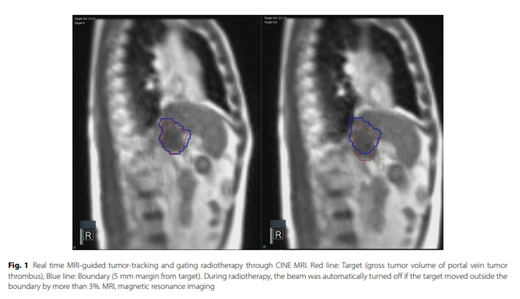

[Radiat Oncol .] Magnetic resonance imaging-guided radiotherapy for portal vein tumor thrombus in hepatocellular carcinoma: outcomes and prognostic factors간세포암 문맥종양혈전에서 자기공명유도영상 유도 방사선치료 결과와 예후인자가톨릭의대 / 이소정, 김명수*

Background: High-dose prescribed radiotherapy has been attempted to improve local control and restore portal vein in patients with hepatocellular carcinoma (HCC) complicated with portal vein tumor thrombus (PVTT). The aim of this study was to evaluate feasibility of real-time tumor-tracking magnetic resonance imaging-guided radiotherapy (rtMRgRT) for PVTT in HCC. In addition, prognostic factors for overall survival (OS) and progression pattern after radiotherapy (RT) were analyzed.Methods: We retrospectively reviewed the data of 34 patients who had unresectable HCC complicated with PVTT and who were treated with rtMRgRT using hypofractionated radiotherapy (HFRT) and stereotactic body radiation therapy (SBRT) between June 2019 and October 2023. HFRT was performed with a total of 50-60 Gy in 10 fractions, and SBRT was performed in a range of 36-50 Gy in 4-5 fractions. The median biologic effective dose with an a/b ratio of 10 was 100 Gy10 (range: 68.4-100 Gy10).